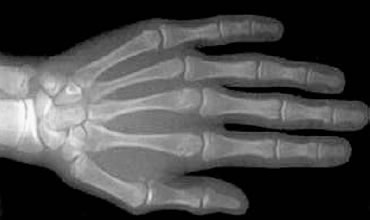

Radiografia de Mão e Punho

Auxiliar nos tratamentos ortodônticos/cirúrgicos. Avaliação da maturidade óssea e previsão do estágio do crescimento da criança e adolescente.